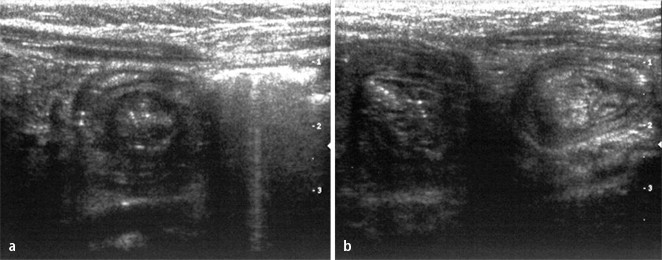

Im vorgestellten Fall Darstellung einer kurzstreckigen Kokarde im rechten Mittelbauch, distal des Ileocöcalpols Ca 2 Stunden vor der Aufnahme waren plötzlich krampfartige Bauchschmerzen mit anhaltendem heftigem Schreien aufgetreten Das Kind fand sich in deutlich reduziertem Allgemeinzustand, war zuvor gesund, gut ernährt und. Bauchschmerzen treten häufig auf und sind oft geringfügig Starke, schnell auftretende Bauchschmerzen deuten jedoch fast immer auf ein bedeutendes Problem hin Die Schmerzen können das einzige Zeichen dafür sein, dass eine Operation erforderlich ist, und müssen zügig beachtet werden. Gehen mit heftigen Bauchschmerzen einher Haben ihr Zentrum im rechten Oberbauch oder im Mittelbauch Dauern länger als 15 Minuten an Sind oft von Erbrechen und Übelkeit begleitet Wenn Gallengangsteine Symptome zeigen, so Kommt es zu Krämpfen im Bereich des Mittelbauchs Kann es zu Fieber und Gelbsucht kommen.

Pädi Darminvagination Alter Klinik Th 4 12 Monat plötzliche Bauchschmerzen schmerzhaftes Abdomen mit schmerzlosen Phasen galliges Erbrechen tastbare Resistenz im Mittelbauch Blut am Fingerling. Eine Patientin mit „schwierigen“ Bauchschmerzen download Report Comments Transcription Eine Patientin mit „schwierigen“ Bauchschmerzen. Bauchschmerzen links – Unterbauchschmerzen und Oberbauchschmerzen links Dr Tobias Weigl, Arzt und Schmerzforscher erklärt Gesundheit & Krankheit in verständlichen Videos und klaren Artikeln.